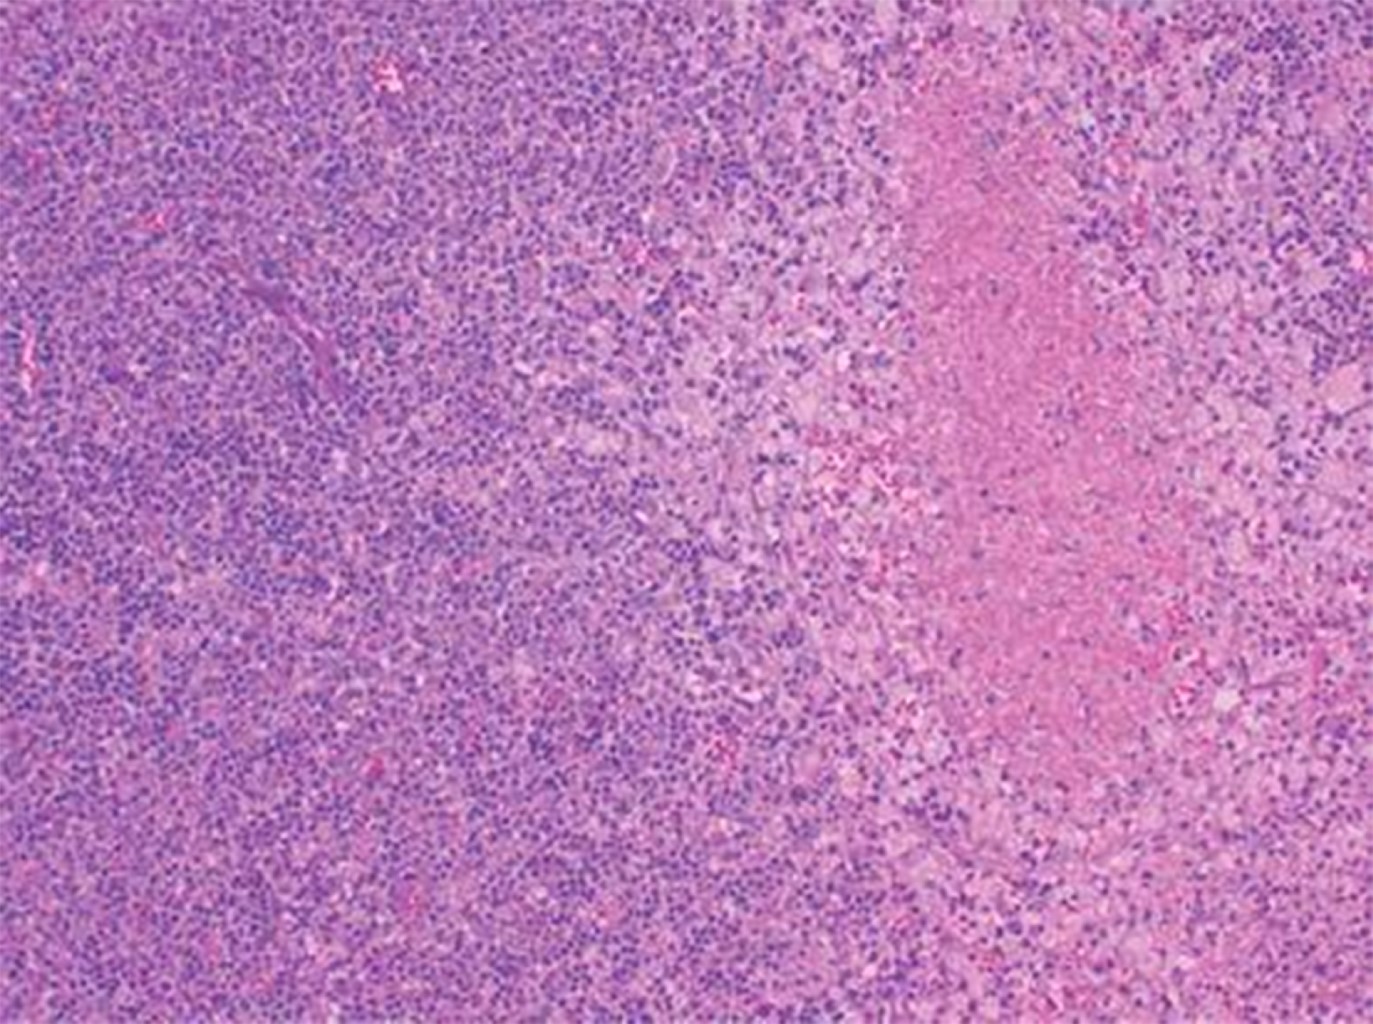

Enfermedad De Kikuchi Fujimoto